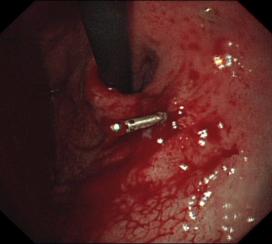

5. ERCP及相关治疗(经十二指肠镜胆道取石、乳头括约肌切开术EST、括约肌切开取石及蛔虫ECT、鼻胆管引流术ENBD、鼻胰管引流术ENPD、胆管狭窄扩张术、胆胰管支架安置术):治疗胆管结石,胆道蛔虫,胆管、胰管狭窄,化脓性胆管炎,梗阻性黄疸,晚期胆管癌、胰头癌,胰管结石,重症胰腺炎等;

胆石症ERCP治疗